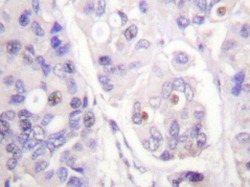

Supportive validation

- Submitted by

- Acris Antibodies GmbH (provider)

- Main image

- Experimental details

- Immunohistochemical analysis of human breast carcinoma tissue (Formalin- fixed Paraffin-embedded) using CDC16 / APC6 antibody (Cat.-No. AP20213PU-N).